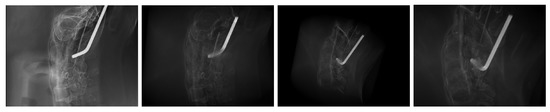

2.4. Image Data

3. Results